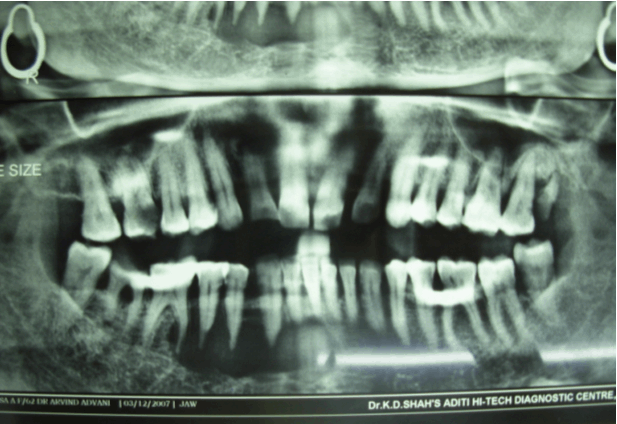

A 63-year-old female patient (Indian) was referred to the Department of Oral and Maxillofacial Pathology, Government Dental College and Hospital, Mumbai, Complaining of an asymptomatic swelling in the right anterior region of mandible that was present since approximately three months. The clinical examination revealed a painless, non-tender swelling over the right parasymphysis region of mandible along with slight facial asymmetry. The mucosa overlying the lesion was normal with expansion of both the cortical plates and showed obliteration of the labial vestibule (Figure 1). The Panoramic radiograph revealed a well-defined multilocular radiolucency from the lower left side central incisor to the right first molar (Figure 2). Calcifications was not clearly evident on radiograph. On aspiration a blood tinged fluid was seen. The clinical diagnosis of an odontogenic cyst was made and an incisional biopsy was obtained from the right parasymphysial area to establish a definitive diagnosis. The differential clinical diagnosis included muticystic ameloblastoma and odontogenic keratocyst.

Figure 2: A well-defined multilocular radiolucency from the left side central incisor to the right first molar of Mandible (Panoramic Radiograph).